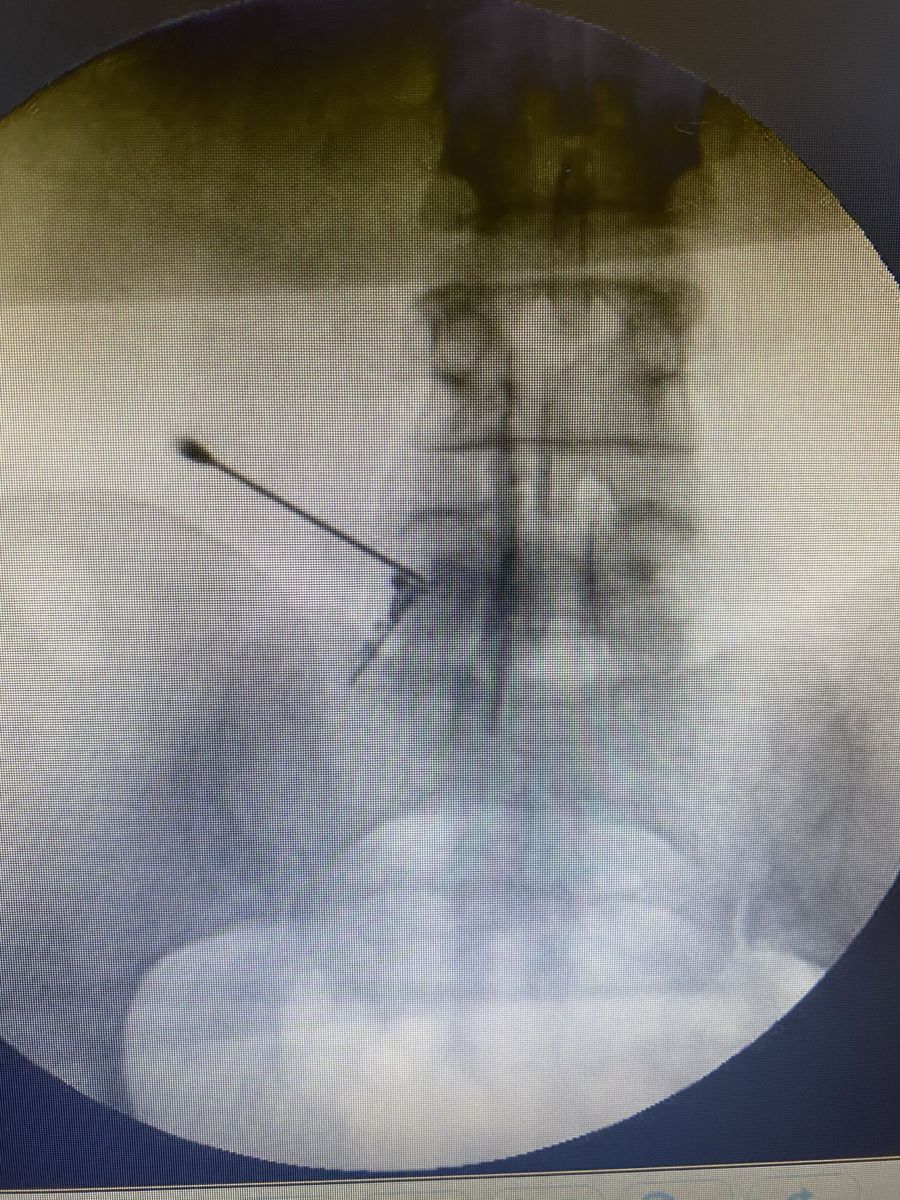

Aguja posicionada bajo fluoroscopia

Posición precisa de la aguja bajo fluoroscopia. Esto aumenta la eficacia y ayuda a reducir riesgos.